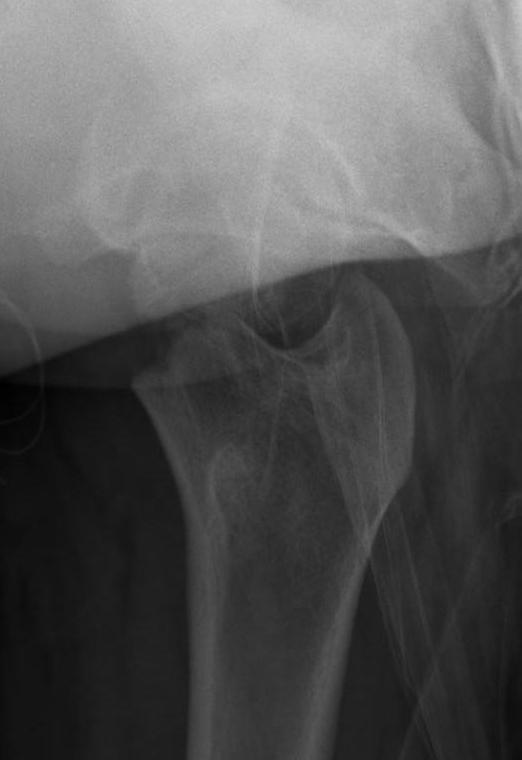

Type 3

- basicervical

- second most common 30%

- AVN 30%

Type III

Undisplaced

Hip spica v ORIF

- displacement a risk

- can leave fixation short of physis

Displaced

Closed reduction

- < 3 years K wires

- > 3 cannulated screws / pediatic hip screw

Spica post op < 10 years